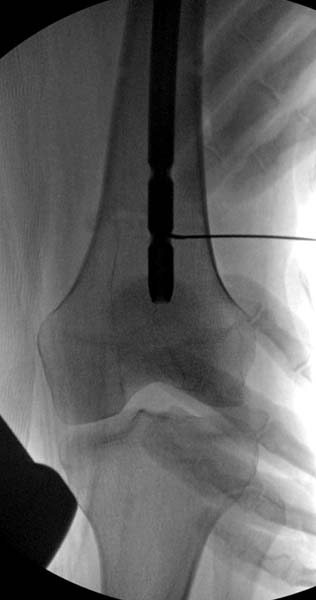

> стабильная.. На третьий день провели стабилизацию перелома бедра

> антеградным остеосинтезом.

> Закрытый БИОС решает множественные проблемы связанные с лечением

> переломов, но проблема дистальной блокировки без рентгена до сих пор

> остается нерешенной. Рекламированные производителями приспособления для

> дистальной блокировки из-за различной кривизны кости не эффективны или

> стоит очень дорого (Smith&Nephew SureLock). Задержка операции из-за

> блокировки не всегда удовлетворяет, и многих вынуждает искать